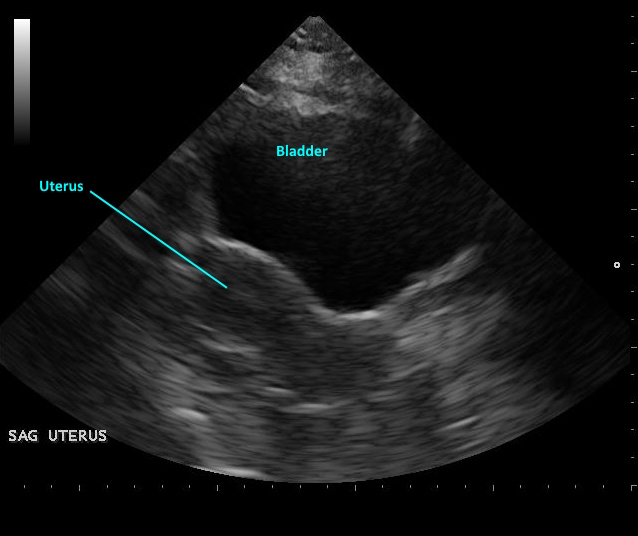

View-by-view acquisition guidance for pelvic and gynecologic ultrasound, aligned with current AIUM guidelines. Guides transabdominal and transvaginal technique with image optimization tips and normal measurement criteria for uterine and adnexal evaluation.